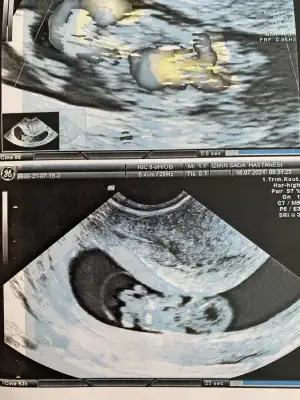

Erkek gibiBuda benim yorumlayabilirmisin![]()

Belkide erkektir ben USG göre tahmin ediliyorum Dr gibi detaylı bakmıyorum kaç haftalık ta tahmin etti DrDoktor üçtür erkeğe benziyor ama net değil diyor demekki kız![]()

Buda yeni USG mi